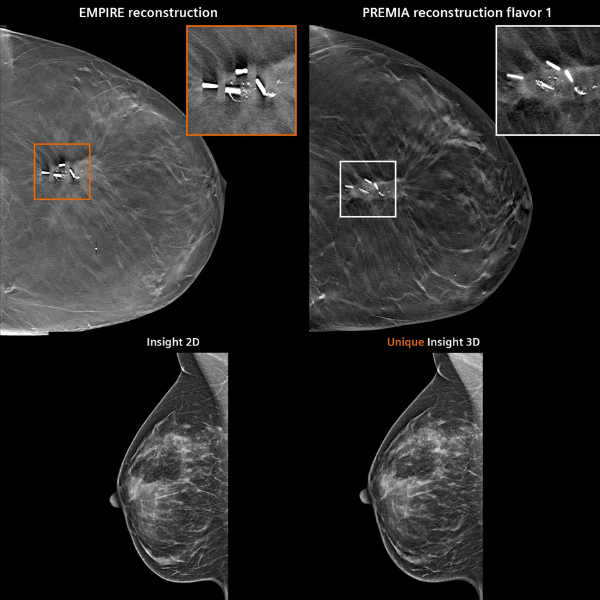

Gracias a la innovadora tecnología PlatinumTomo, el MAMMOMAT B.brilliant ofrece una adquisición avanzada de imágenes por tomosíntesis, mejorando la visualización de lesiones y reduciendo la superposición de tejidos. Su escaneo ultrarrápido, con tomosíntesis de gran angular de 50° en solo 5 segundos, optimiza el flujo de trabajo y mejora la comodidad de la paciente durante el estudio.

El sistema proporciona excelente resolución en plano y mayor definición en profundidad, con opciones de impresión de imagen personalizable según las necesidades clínicas. Su diseño ergonómico e interfaz intuitiva están pensados para maximizar la eficiencia del técnico radiólogo y la seguridad del paciente.